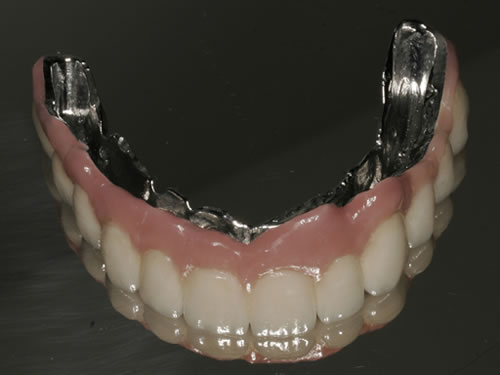

Diese Beispiele ließen sich endlos fortführen. Sie zeigen die Probleme bei der Versorgung zahnloser Kiefer, wie sie immer wieder geschildert werden. Mit Hilfe sehr einfacher Maßnahmen kann durch die Einpflanzung künstlicher Zahnwurzeln eine instabile Prothese soweit befestigt werden, dass die Kau- und Sprechfunktion wieder hergestellt ist. Manchmal kann die alte Prothese weiterverwendet werden, in dem man in die Prothesenbasis Sekundärteile einarbeitet, die für Halt sorgen (Abb. 3.5, 3.6). Bei aufwendigeren Steg- oder Teleskoparbeiten muss auch der Zahnersatz der auf den Implantaten fixiert wird neu angefertigt werden. Diese Arbeiten werden dann brückenartig und sehr grazil gestaltet. (Abb. 3.7 bis 3.12).

Abb. 3.8: Individuelle Stegversorgung aus Gold auf vier Implantaten im zahnlosen Unterkiefer.